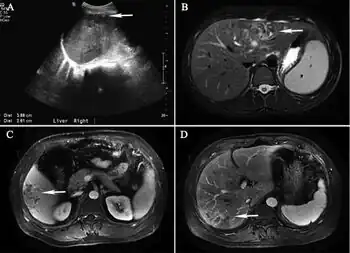

Diagnosis

As to the diagnosis of Hepatic capillariasis the epidemiological history, and clinical manifestations, are taken into account as well as:[4]

- Ultrasound

- MRI

- Liver tissue biopsy